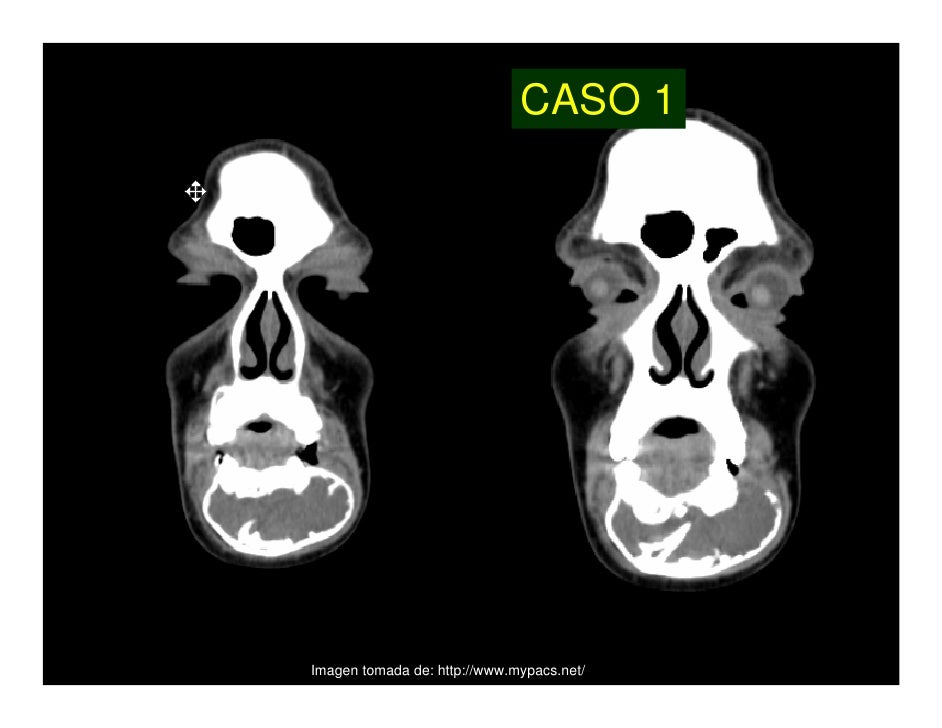

El mixoma odontológico o fibromixoma odontogénico es una neoplasia benigna que se origina en la porción mesenquimatosa del germen dental, ya sea en la papila dental, folículo o ligamento periodontal y se encuentra constituido por células con un abundante estoma mucoide. El mixoma odontológico está normalmente asociado a dientes no erupcionados o ausentes. Histológicamente es una lesión constituida por escasas células de morfología estelar o fusiforme inmersas en un estroma mixoide abundante. Las células tumorales presentan un núcleo pequeño y picnótico y suelen mostrar prolongaciones citoplásmicas elongadas que se anastomosan con el citoplasma de las células adyacentes. El estroma mixoide intercelular está compuesto por una matriz rica en mucina (mucopolisacáridos ácidos, fundamentalmente ácido hialurónico y en menor proporción, condroitín sulfato).